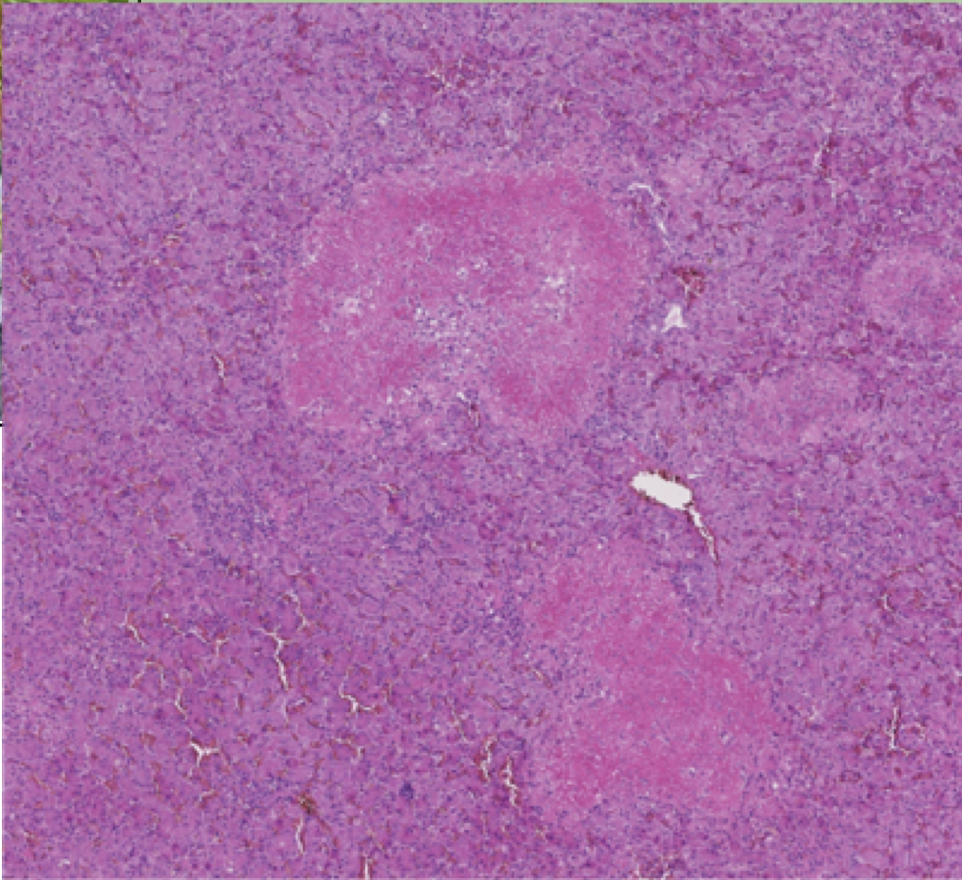

What is the morphologic diagnosis of this gross image? What condition has gross morphology like this?

Acute, severe, multifocal necrotizing hepatitis.

You can also say -> acute diffuse severe fibronous pericarditis.

Psittacosis